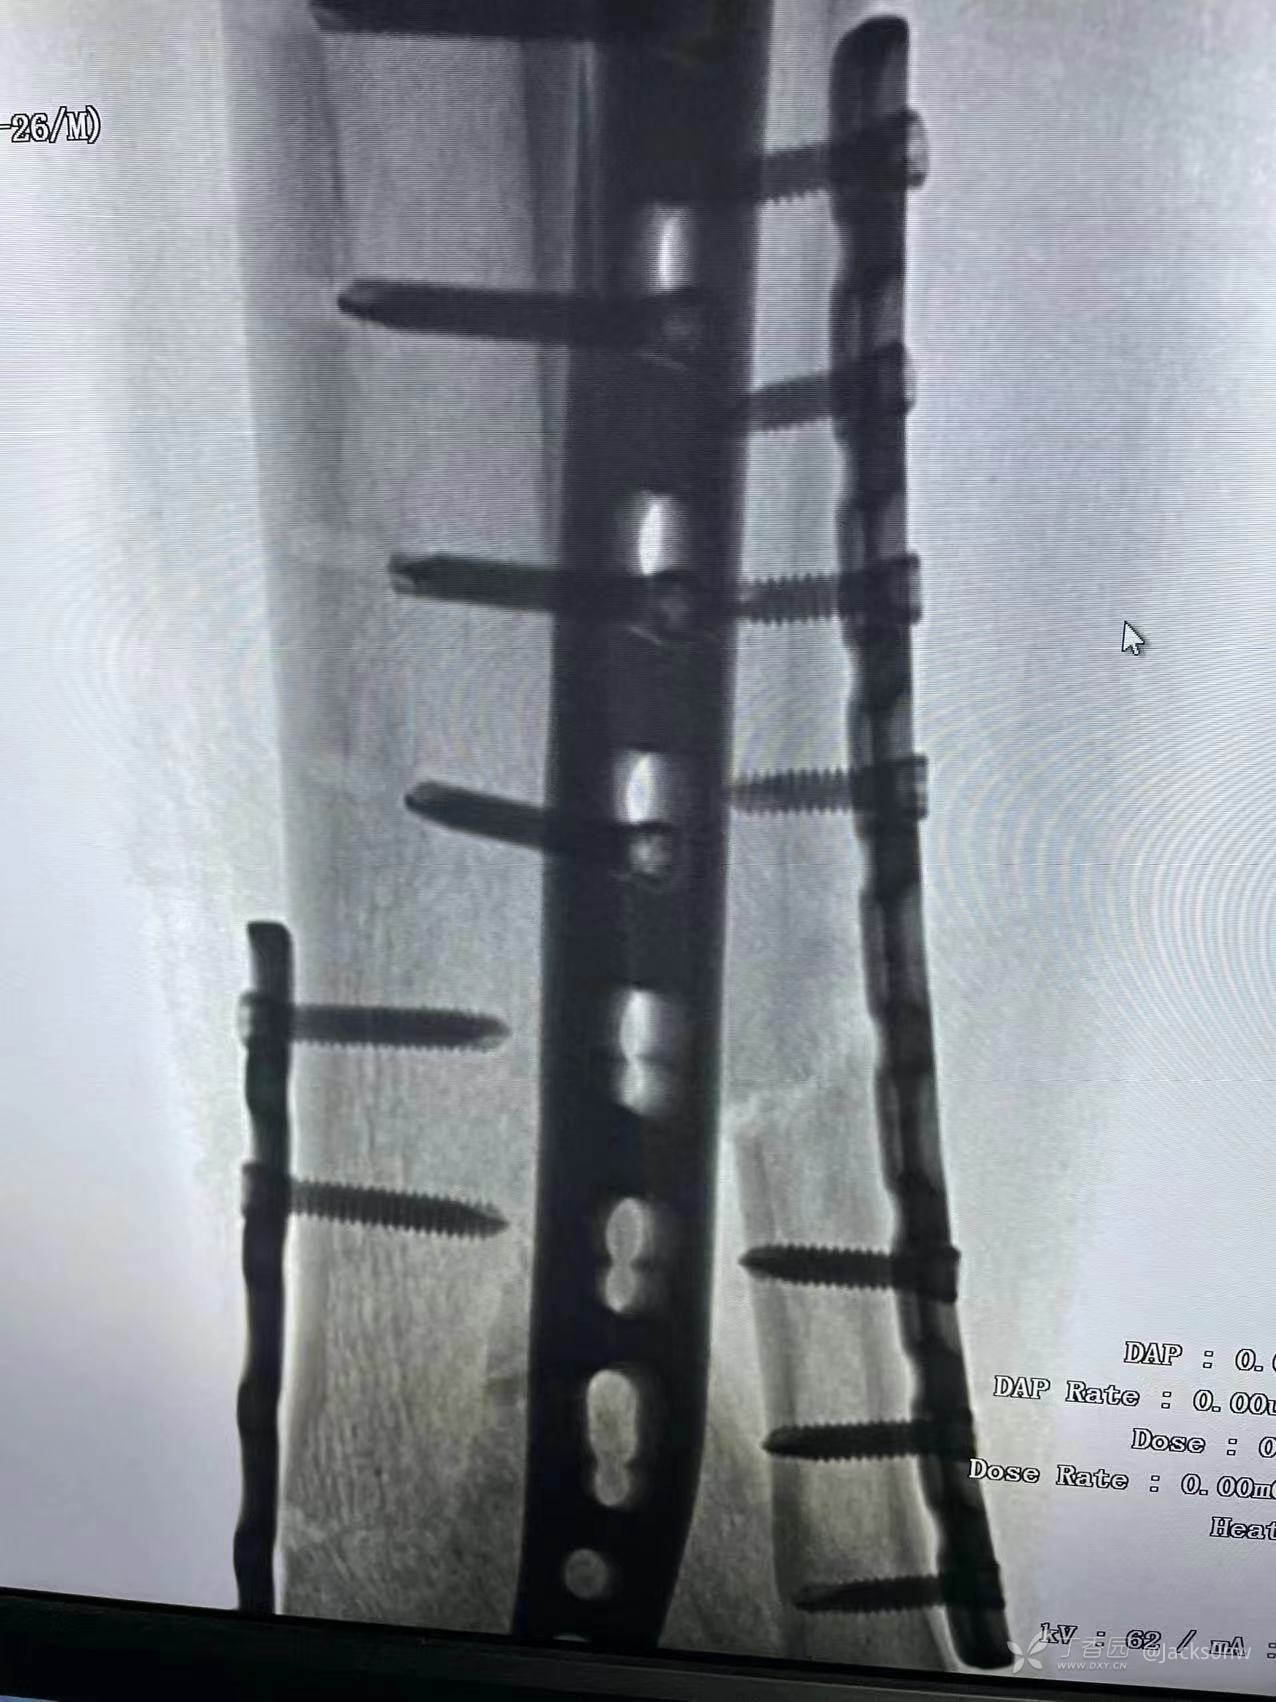

术中

2022年10月26 14时行左胫骨远端(Pil0n)粉碎性骨折切开复位钢板螺钉内固定术+左腓骨中下段粉碎性骨折切开复位钢板螺钉内固定术+神经血探查术+骨筋膜室综合征切开减压术+骨移植术+高分子夹板外固定术。

术后